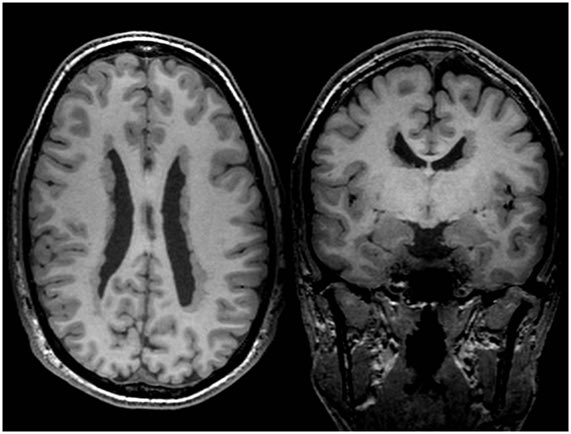

Las heterotopias nodulares periventriculares son un tipo de malformación del desarrollo cortical que causan epilepsia fármacorresistente. En esta RM T1 podemos ver los nódulos de sustancia gris ectópica en la pared de los ventrículos cerebrales. #Epitecaproject #Neuroteaching

EpilepsiaRuber's tweet image. Las heterotopias nodulares periventriculares son un tipo de malformación del desarrollo cortical  que causan epilepsia fármacorresistente. En esta RM T1  podemos ver los nódulos de sustancia gris ectópica en la pared de los ventrículos cerebrales.